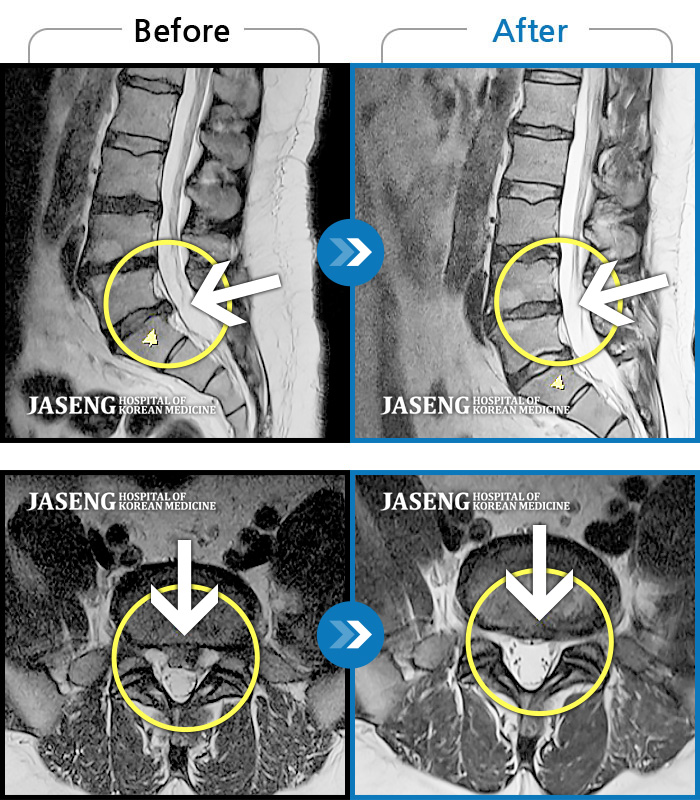

허리디스크

광주 · 장영우 원장

양측 허리부터 골반 묵직한 통증, 좌측 다리 외측까지 이어지는 당기는 통증으로 내원하셨습니다.

촬영시기

2503.04.01 ~ 2509.11.01

2025.09.22